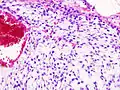

| Histopathologic image of chondrosarcoma of the chest wall. Surgical resection of recurrent mass. H & E stain. | |

Imaging studies – including radiographs ("x-rays"), computerized tomography (CT), and magnetic resonance imaging (MRI) – are often used to make a presumptive diagnosis of chondrosarcoma.[9] However, a definitive diagnosis depends on the identification of malignant cancer cells producing cartilage in a biopsy specimen that has been examined by a pathologist. In a few cases, usually of highly anaplastic tumors, immunohistochemistry (IHC) is required.